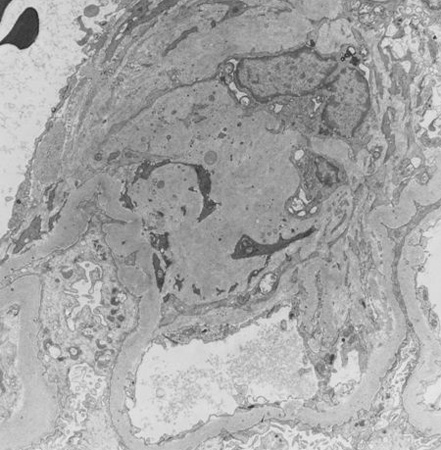

Doença renal diabética

Doença renal diabética: na posição de 12 horas - nódulos de Kimmelstiel-Wilson no início, uma forma arredondada de expansão mesangial

Do acervo do Dr. Raoul Fresco; usado com permissão